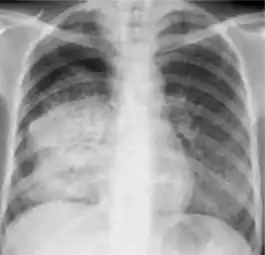

Chest x-ray showing bilateral hilar adenopathy of primary pulmonary TB